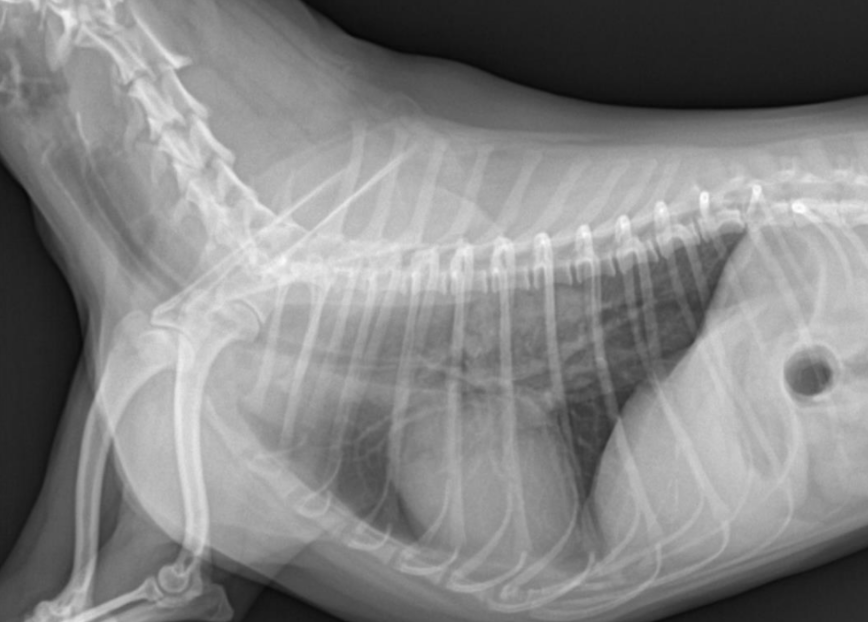

์ํ์ฅ : GD vs. GDV

- ๊ฐ๋ณ์ key point๋ pylorus์ ์์น & ์์ ๋ถํํ(compartmentalization) !

- ์ ์์ ์ธ ์์น๋ ์ธ์ธก์์์ ์๋์ชฝ, ๋ณต๋ฐฐ์์์ ์ผ์ชฝ์ ์์น.

- GD๋ ์๊ฐ ํ์ฅ๋์ด ์์ผ๋, ์์น๋ ๊ทธ๋๋ก.

- GDV๋ ์ฅ์ด ๊ผฌ์ด๋ฉด์ ์์น๊ฐ ๋ฌ๋ผ์ง๋ฏ๋ก, pylorus์ ์์น๊ฐ ์ธ์ธก์์์ ์์ชฝ

| GD | GDV | |

|---|---|---|

| VD | - greater curvature ์ผ์ชฝ(์ ์) * 360๋ ํ์ ์์๋ ์ผ์ชฝ์ ์์น | - greater curvature ์ค๋ฅธ์ชฝ (180๋ ์ผ์ ) - duodenum ์์น๋ ํจ๊ป ๊ผฌ์ |

| RL | - pylorus๊ฐ ์๋์ชฝ(์ ์) | - pylorus ์์ชฝ - ์์ ๋ถํํ(compartmentalization) : ๋ถ๋ฐฉ ํ์ธ - gastric band (soft tissue) ๊ด์ฐฐ |

![]() ![]() | ![]() ![]() | |

[๋ถํํ]![]() ![]() |